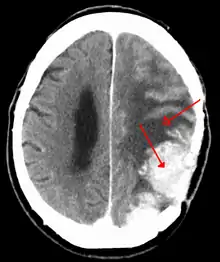

| A contrast-enhanced CT scan of the brain, demonstrating the appearance of a meningioma | |